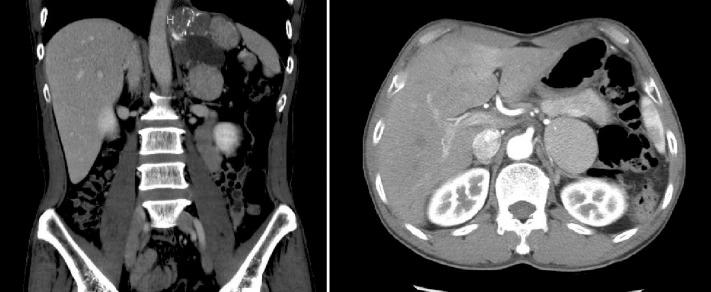

Extralobar pulmonary sequestration mimicking an adrenal tumor.

Pulmonary sequestration is a rare cystic malformation composed of bronchopulmonary tissue that is discontinuous from the tracheobronchial tree and has an anomalous systemic blood supply. We present a case of a 40-year old male who presented with an extralobar pulmonary sequestration and underwent a laparoscopic retroperitoneal mass excision. Preoperative imaging revealed a large 11.3-cm retroperitoneal tumor consisting of a multiloculated cystic lesion. The patient was discharged home, and at 3-mo follow-up no complaints were reported.